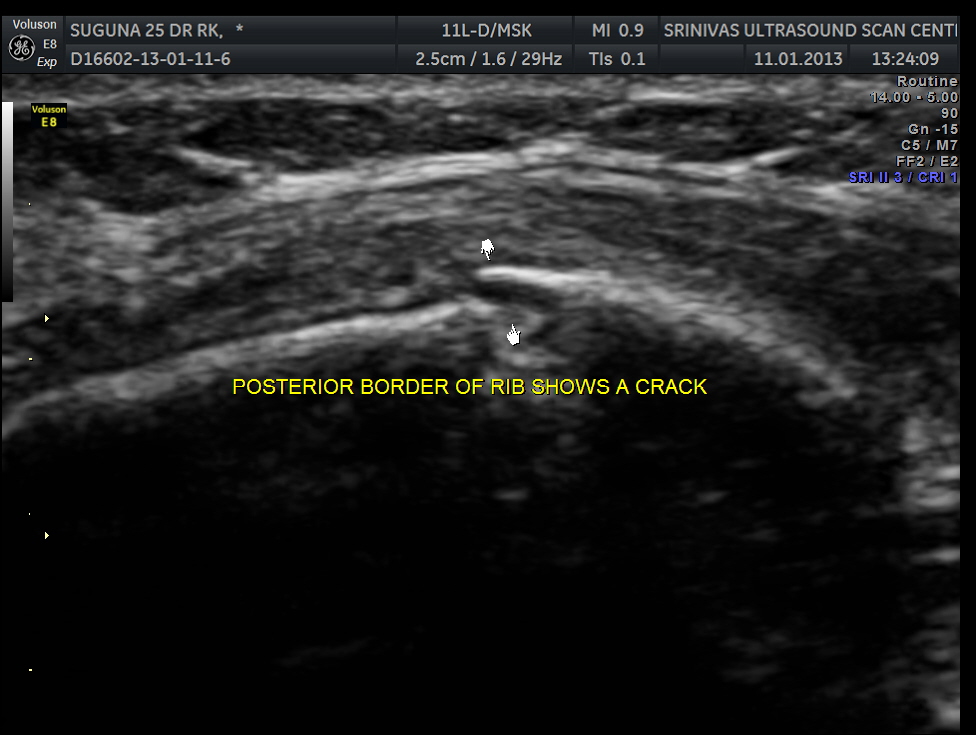

This was a 25 year old lady who fell on her chest while a cow was chasing her . She had persistent severe pain in the left side of the chest. Xray of the rib cage was reported as normal and appeared to be normal.

Scan over the point of maximal tenderness ( over the 6th rib on the left side anteriorly) revealed a crack in the bone on the posterior aspect . Probably as it was not a complete fracture it was missed on the xray.

The images are shown below